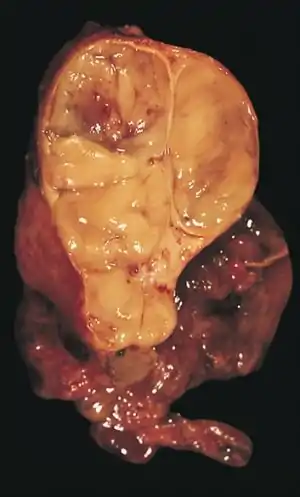

An encapsulated thymoma (mixed lymphocytic and epithelial type)

Thymoma originates from the epithelial cell population in the thymus, and several microscopic subtypes are now recognized.[1] There are three principal histological types of thymoma, depending on the appearance of the cells by microscopy:

Thymic cortical epithelial cells have abundant cytoplasm, vesicular nucleus with finely divided chromatin and small nucleoli and cytoplasmic filaments contact adjacent cells. Thymic medullary epithelial cells in contrast are spindle shaped with oval dense nucleus and scant cytoplasm thymoma if recapitulates cortical cell features more, is thought to be less benign.